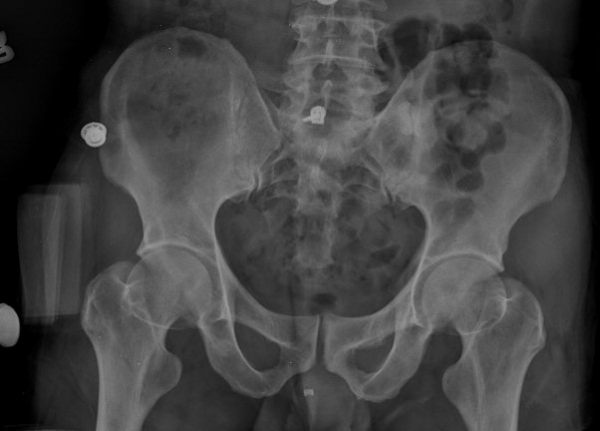

¾ûµ¢ÀÌ °üÀý Á¾´Ü¸é°Ë»ç¿¡¼­ ƯÀÌ ¼Ò°ßÀ» º¸ÀÌÁö ¾ÊÀ½(»çÁø 1).

ÃÊÁø ½Ã ½ÃÇàÇÑ ¹æ»ç¼± ÃÔ¿µ»ó ÀüÇÏÀ屨 ºÎÀ§¿¡¼­ ¼®È¸È­ À½¿µÀÌ °üÂûµÇ°í, 3ÁÖ ÈÄ ½ÃÇàÇÑ ÃÔ¿µ¿¡¼­

¼®È¸È­ À½¿µ ¼Ò½ÇÀÌ È®ÀεÊ.